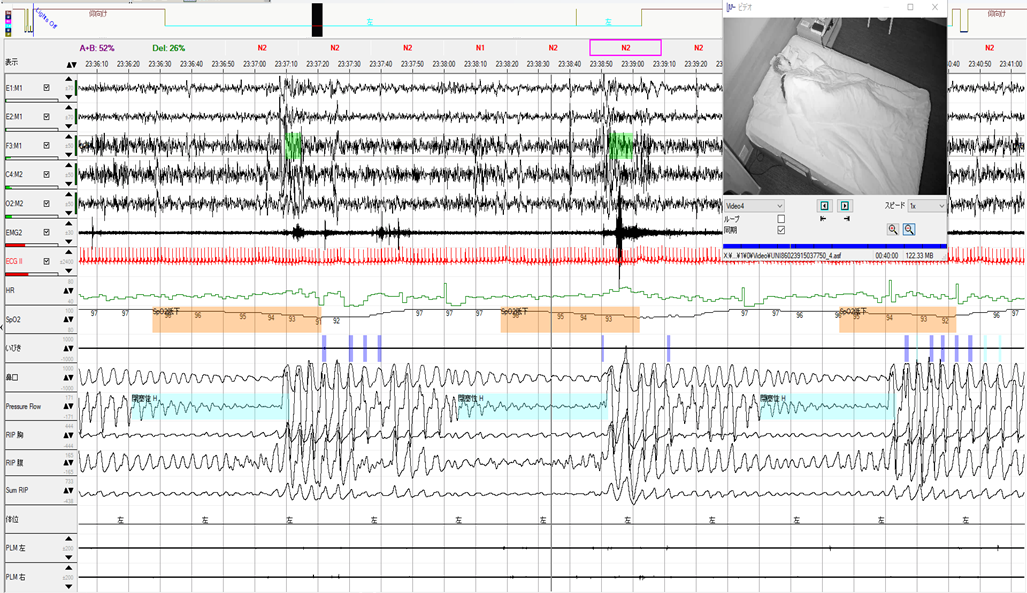

50歳台 女性 身長:156㎝ 体重:45kg BMI18.5 ESS:4 健診で不整脈を指摘され、静脈瘤、下腿浮腫の症状で来院されました。ホルター心電図でCVHRが23回/時間の結果で、さらにいびきの指摘もあり、簡易検査を施行したところREI=13.4回/時間、最低SpO2=88%、2%ODI=25.2回/時間でした。CVHRはAHIとの相関が報告されており、SASスクリーニングとして認識されつつあります。またBMI低値な症例は、呼吸イベントがあってもSpO2低下が軽微なことが多く、2%ODIもSAS評価に有意なパラメータと言えます。診断PSGを行ったところ、AHIは24.4回/時間とCVHRと近似した結果でした。体位依存が明瞭なことは確かですが、22時30分からノンレム睡眠で左側臥位にもかかわらず、一過性に閉塞性低呼吸を認めています(赤下線部分)。

左側臥位時の閉塞性低呼吸波形です。実はBMIが低値ですが、高度の小顎症の症例でした。小顎症は、やせていても重症の無呼吸であることが多く報告されています。顎という入れ物が小さく中に収まる舌が通常の大きさであれば、無呼吸症になる可能性が大きくなります。重症化すれば体位依存も認めなくなることを示唆していると考えられます。